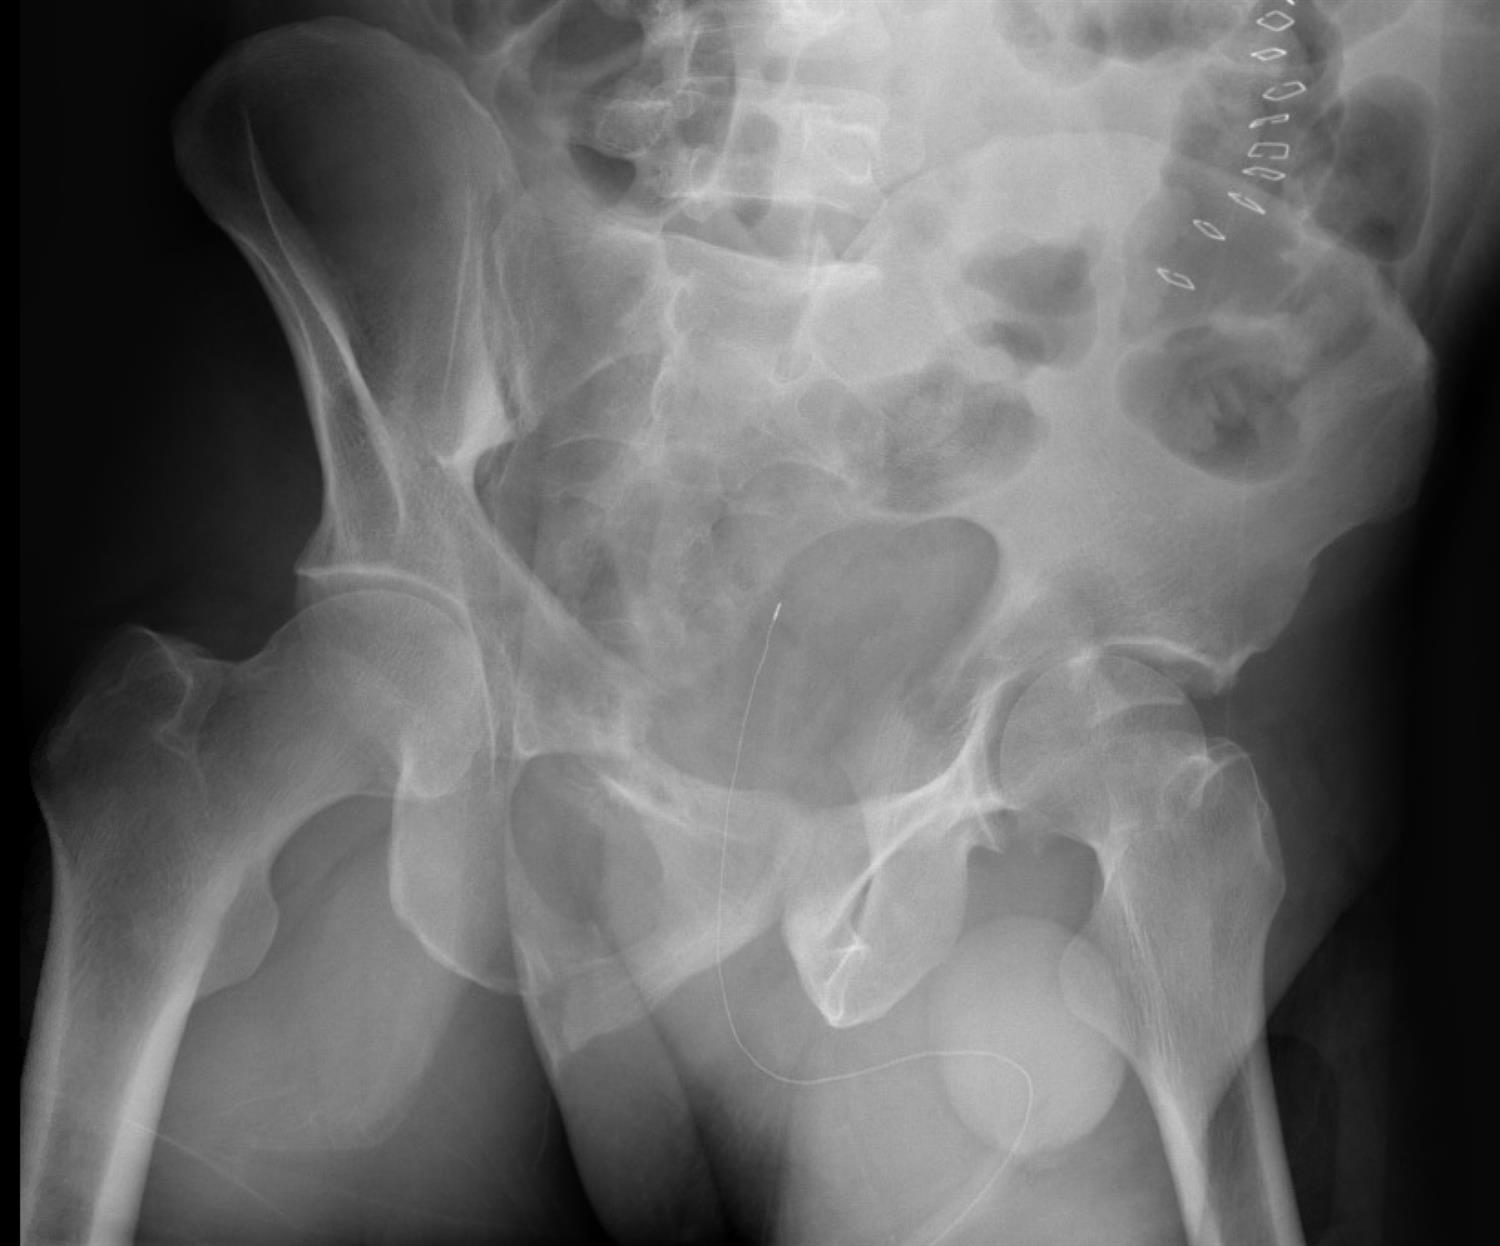

A 33-year-old male presents to the ER after a head-on motor vehicle collision complaining of severe left hip pain. Initial AP pelvis x-rays are shown in Figure A. You wish to further asses his injury pattern by ordering additional radiographs. Which of the following images will be the MOST helpful in visualizing the left posterior column?

The patient has sustained a left anterior column posterior hemi-transverse acetabulum fracture. In order to properly visualize the LEFT posterior column, the most optimal radiographic Judet views would be a left iliac oblique or a right obturator oblique (these are the same image).

Figure A is an AP pelvis showing a left anterior column posterior hemi-transverse acetabulum fracture. Illustration A is an obturator oblique radiograph of the patient in Figure A showing an anterior column fracture. Illustration B and C are Iliac oblique radiographs showing the posterior column of the same patient.